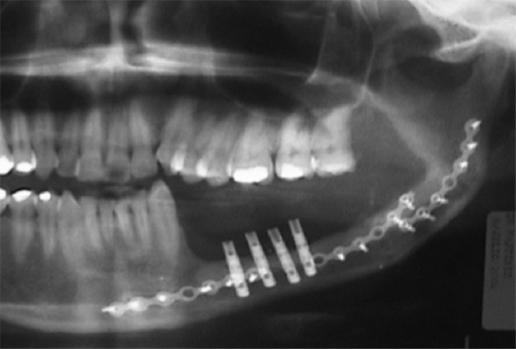

Solo 50 pacientes (68%) tuvieron algún tipo de rehabilitación dental, la gran mayoría con placas externas y cuatro con implantes osteointegrados; todos ellos lograron una rehabilitación adecuada y no hubo pérdida de los implantes en los cuatro pacientes que los recibieron (procedimiento no efectuado en nuestra institución) (Fig. 1).

Figura 1 Los implantes osteointegrados en peroné trasplantado permiten una rehabilitación oral cercana a la normalidad.